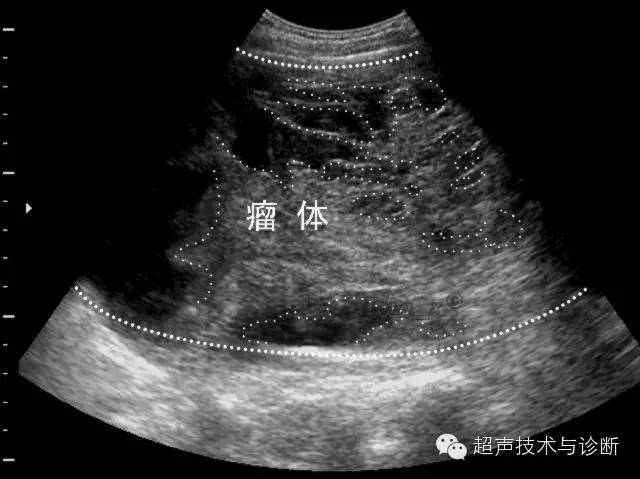

卵巢肿瘤超声大综合

图片尺寸926x317